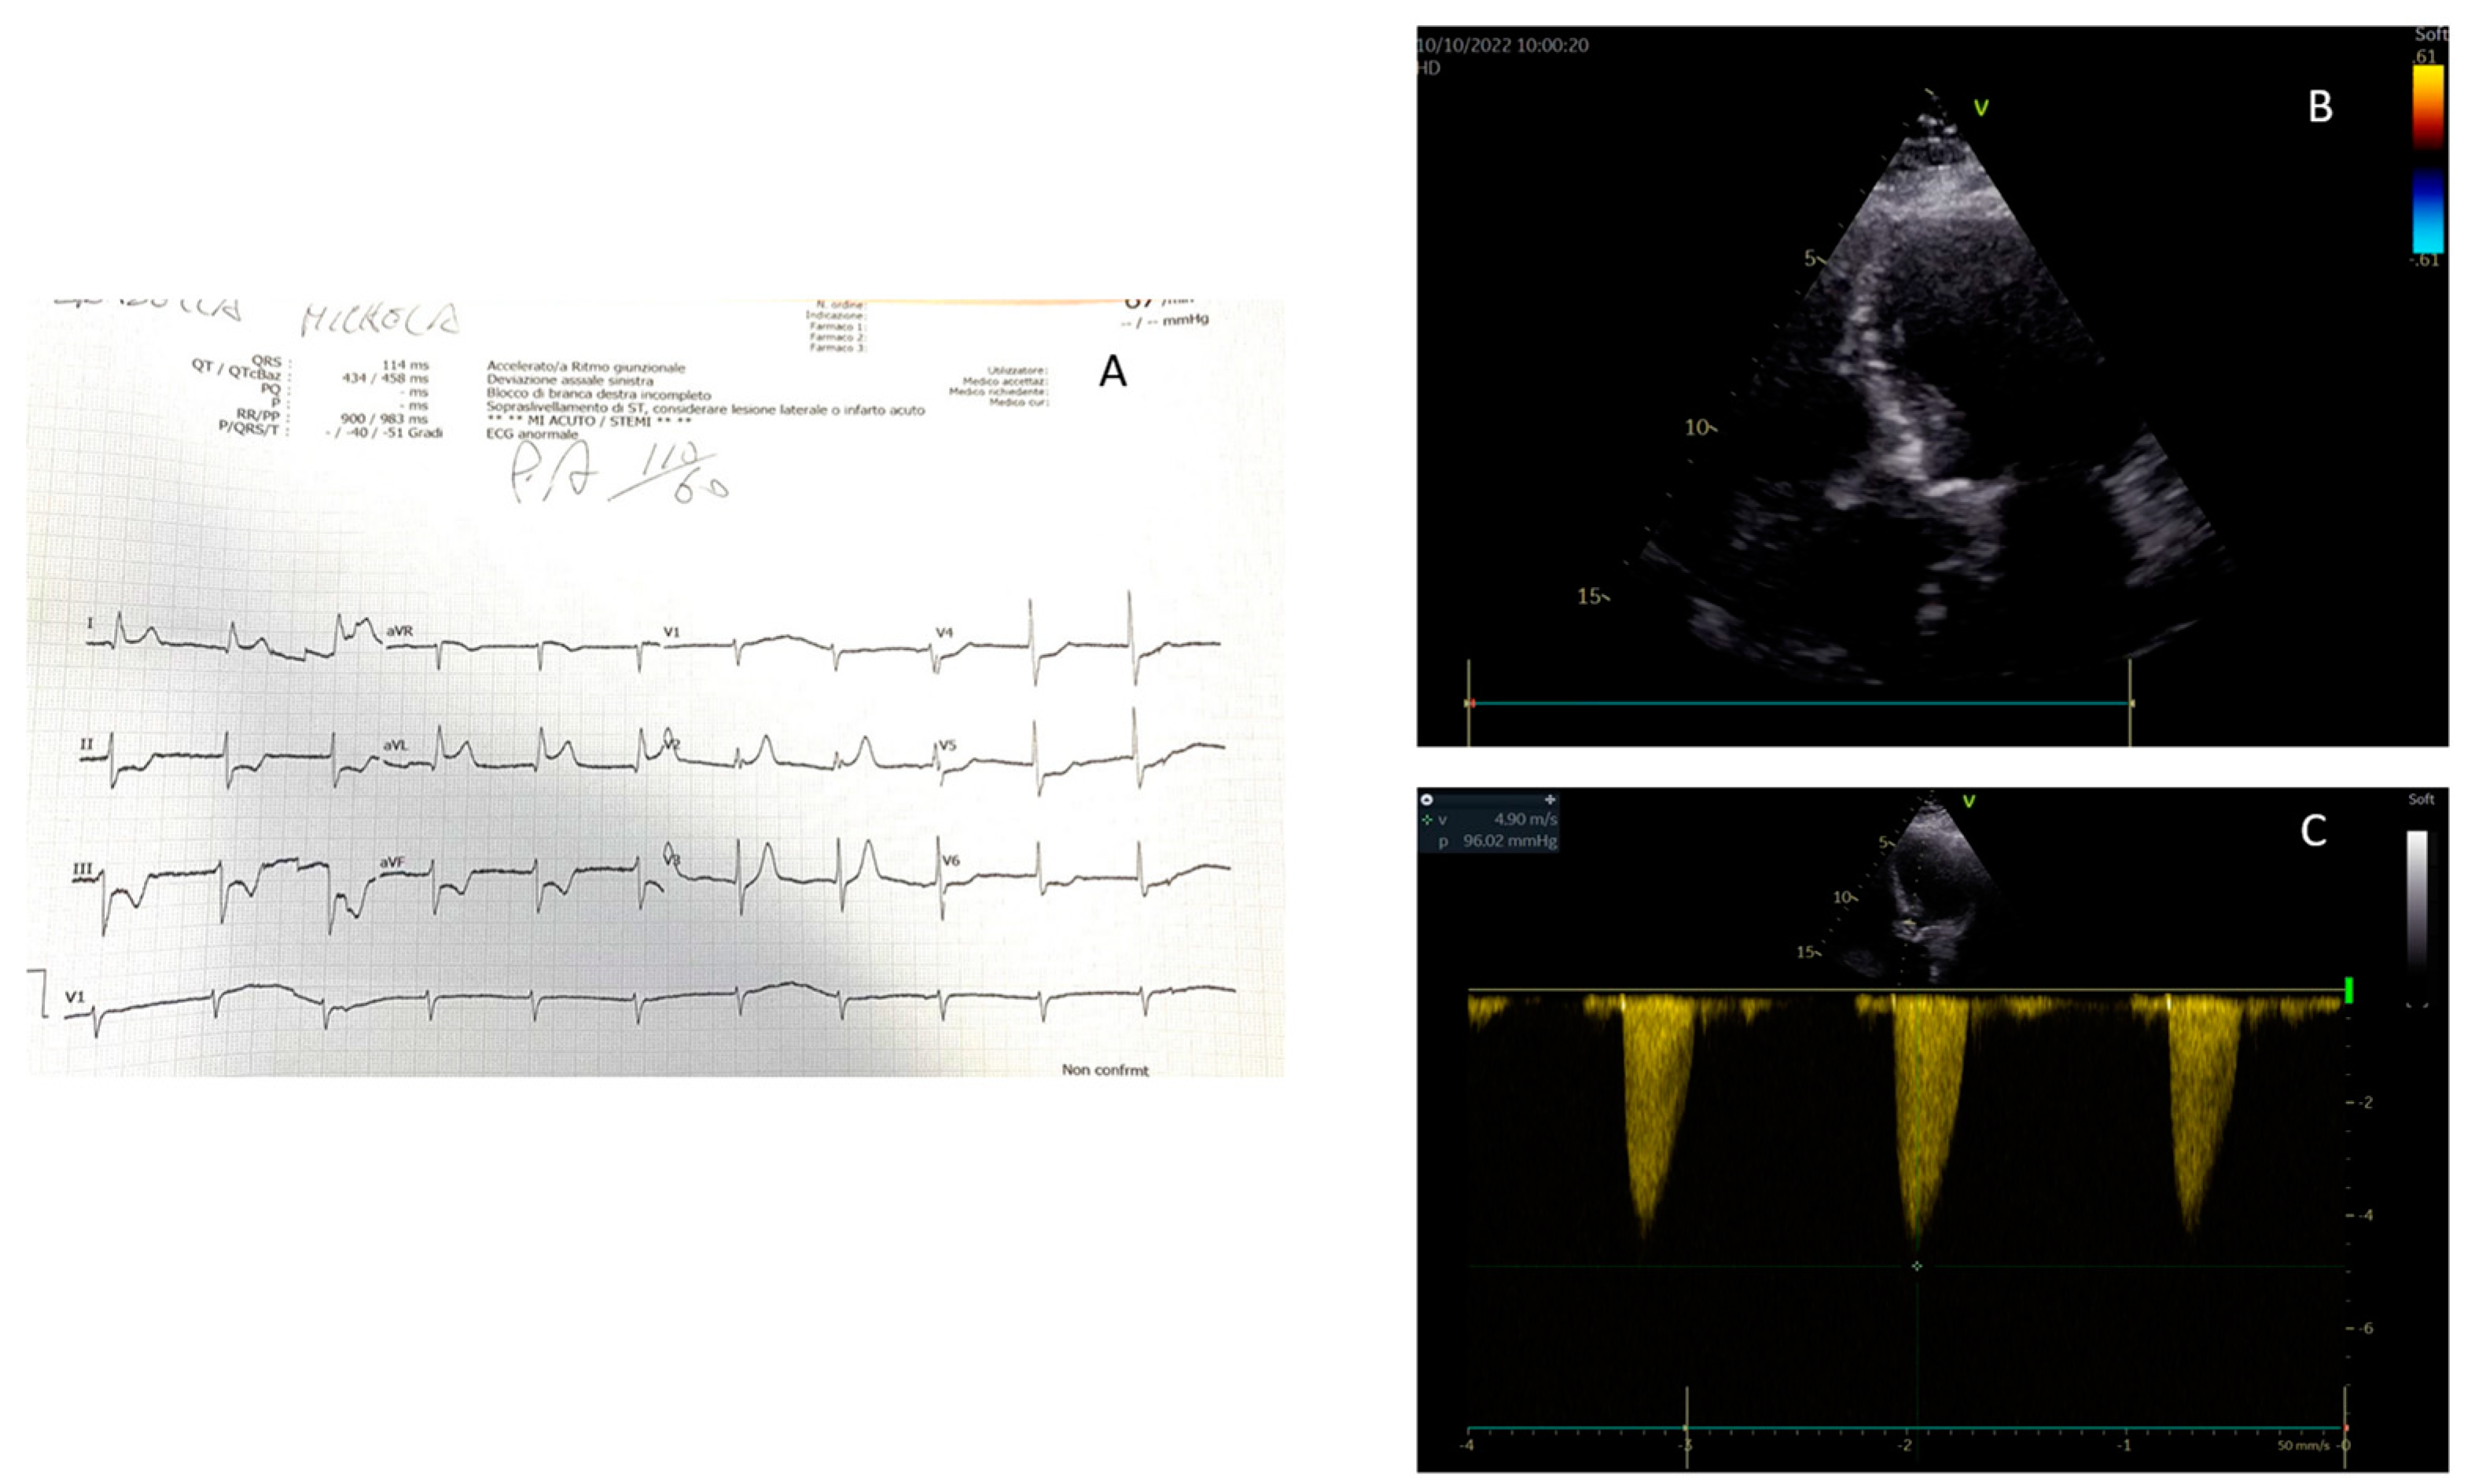

4. Rationale for the Use of Echocardiography for the Diagnosis of STEMI

- Effective in confirming or refuting an electrocardiographic-only diagnosis of STEMI;

- Capable of guiding interventional cardiologists in customizing the revascularization procedure for each patient;

- Useful in stratifying patients with STEMI by identifying categories that require more aggressive treatments or additional pharmacological support beyond the revascularization procedure alone.